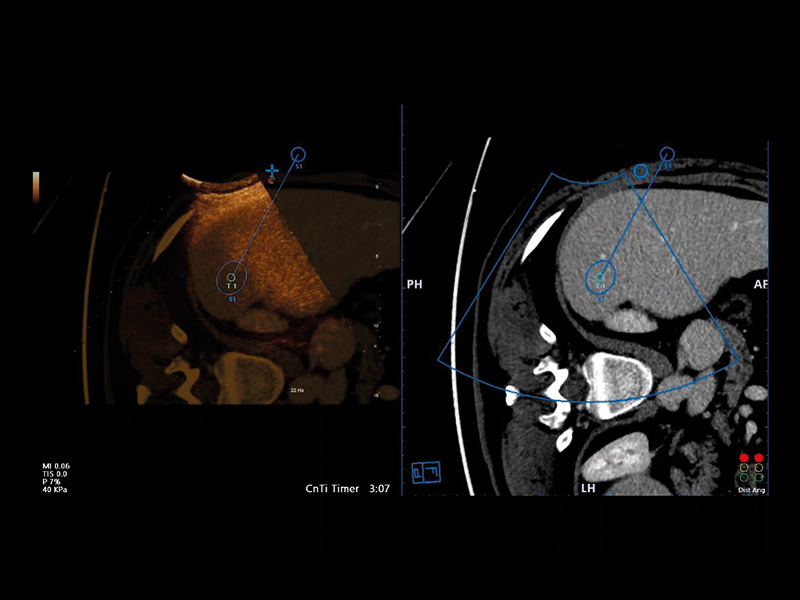

• CnTI™ Clear (Contrast Tuned Imaging): Contrast Enhanced Ultrasound (CEUS) Imaging of Esaote, CnTI™ Clear, detects organ perfusion through contrast agent enhancement to support liver and abdominal lesion characterisations. Based on cutting-edge software, CnTI™ Clear is able to detect low levels of microbubbles, especially in the early arterial phase, while it will ensure their longevity, to give you accurate information on how the lesion is reacting.

Virtual Navigator (VNav), as the most advanced Esaote Fusion Imaging technology supported by Artificial Intelligence, is opening new horizons in cross-modality liver imaging. Virtual Navigator provides a very simple and active coupling of ultrasound examination with a second Dicom modality imaging (MRI/CT/Pet-CT) dataset as a reference. It enables real-time navigation to benefit from both modalities to increase confidence and accuracy throughout interventional procedures on the liver.